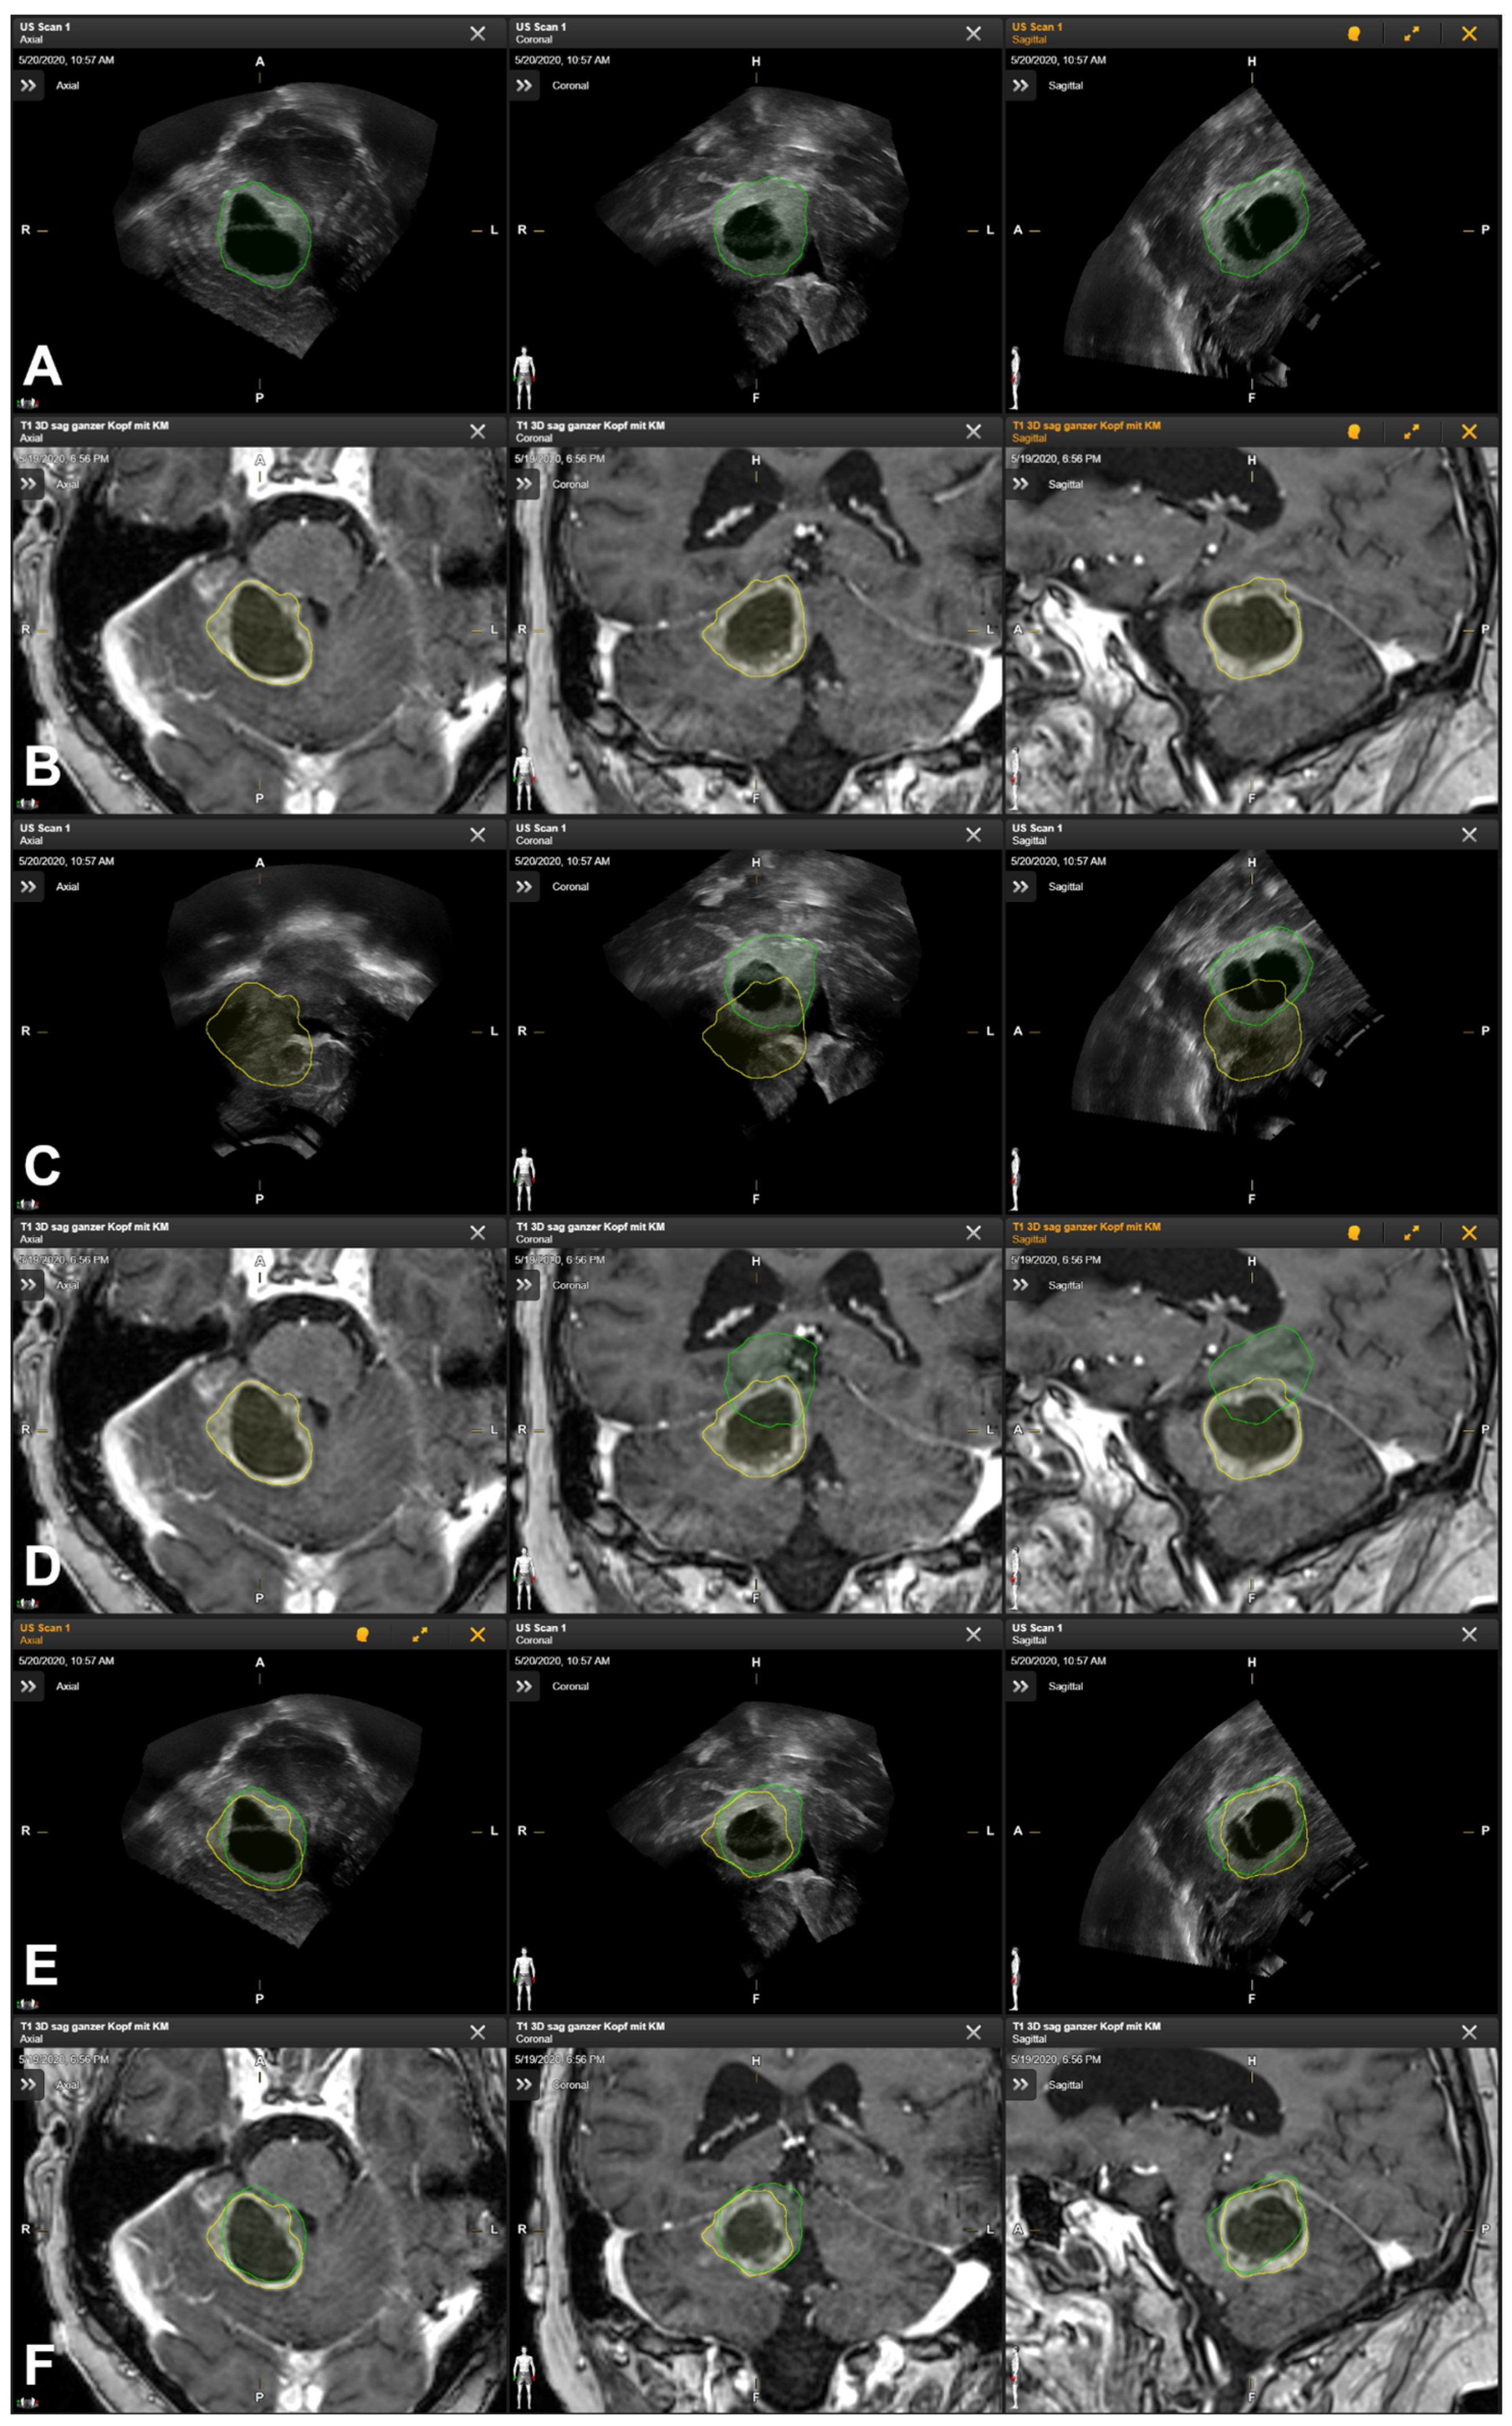

3.5. Illustrative Cases